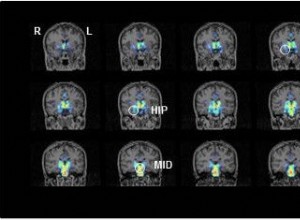

Chimiothérapie et mémoire : des effets durables sur le cerveau des survivants du cancer

L'anesthésie générale chez les bébés : un impact potentiel sur la mémoire à long terme